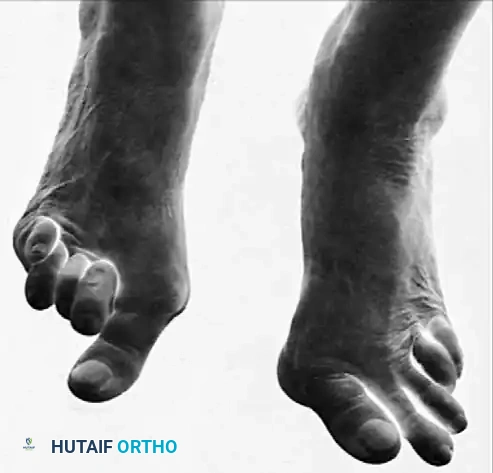

Fig. 81-1 Rheumatoid foot. Note the multiple severe deformities characteristic of rheumatoid arthritis of the forefoot, including advanced hallux valgus, subluxed and dislocated lesser metatarsophalangeal joints, claw toes, hammer toes, and prominent bursal formation.

Fig. 81-4 Multiple deformities of rheumatoid arthritis. Note the prominent bursa directly over the medial eminence and the severe dorsal posturing of the lesser digits.

Fig. 81-6 (A) Heel valgus and foot pronation secondary to RA. If the subtalar and midtarsal joints are surgically reduced, the forefoot may be in pronounced supination relative to the hindfoot, complicating first ray plantarflexion. (B) Radiographic evidence of multiple severe dislocations of the MTP joints.

Fig. 81-2 (A, B) Preoperative clinical views showing severe dorsal subluxation-dislocation of lesser toes. (C) Plantar view post-resection of metatarsal heads. (D) Excellent postoperative clinical alignment following first MTP arthrodesis and lesser metatarsal head excision.